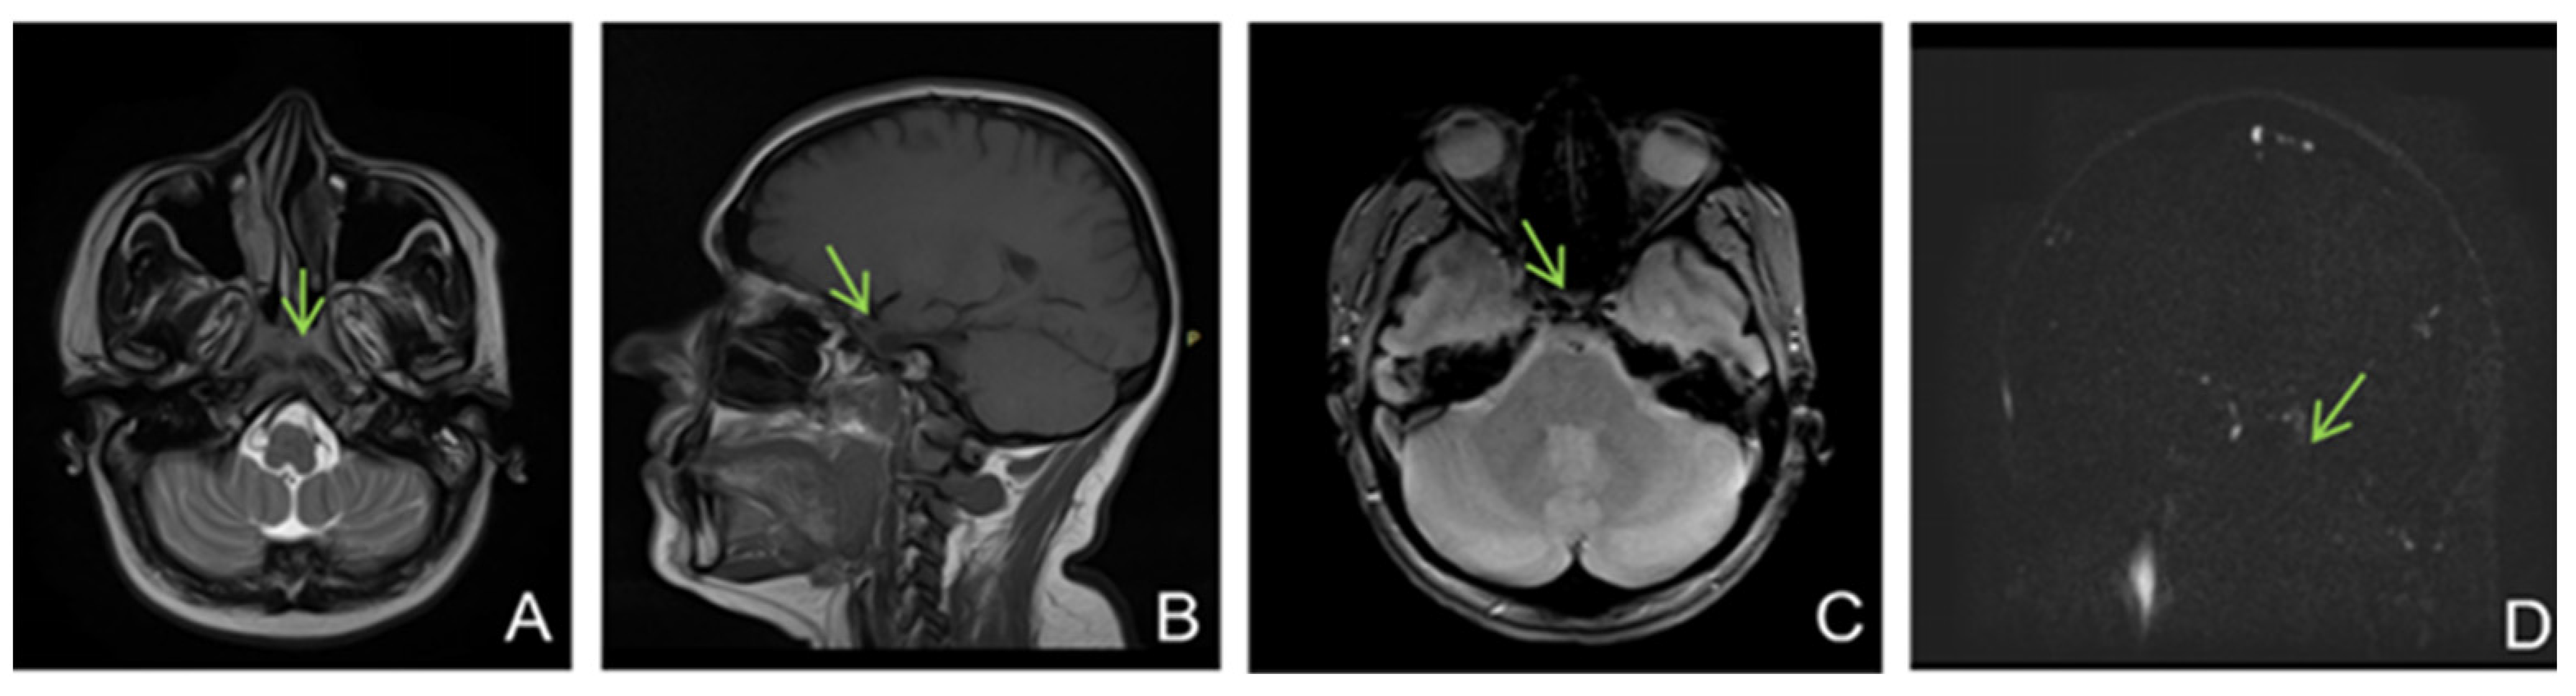

A brain MRI (Figure 5) showed flow asymmetry at the level of the cavernous sinuses, left more than right, coupled with fluid accumulation in the left mastoid cells, whilst cerebral parenchyma had morphology and signals within normal limits, thus establishing the diagnosis of bilateral (left > right) cavernous sinus thrombosis. The patient was started on continuous heparin infusion followed by treatment with acenocoumarol.

Figure 5. Non-enhanced MRI (at onset): ((A)—T2 axial, (B)—T1 sagittal, (C)—T2* axial, (D)—venous TOF coronal) shows unremarkable parenchyma and absence of flow in cavernous sinuses on TOF imagesFive months later, the patient came back to our clinic complaining of paroxysmal episodes of altered state of consciousness with language disorders such as verbal barrage followed by disorientation. An EEG was performed, showing a low-voltage background path, weakly modulated in spindles in the left derivations, reactive when opening the eyes, and rare isolated degraded peak-wave complexes, thus concluding that the patient was experiencing focal onset impaired awareness seizures; she was then started on antiepileptic treatment with oxcarbazepine 300 mg twice daily. She also was psychiatrically examined due to emotional lability confirming the diagnosis of depression and allowing antidepressant treatment to be started.